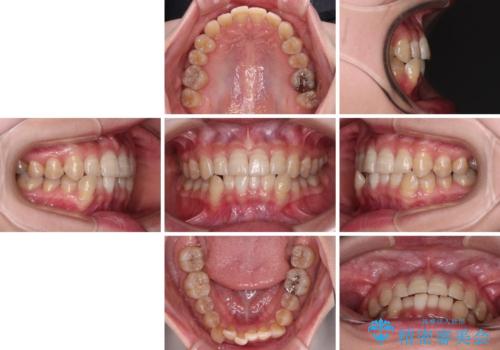

- 下顎の八重歯を気にして来院された患者様です。

マウスピース矯正でもワイヤー矯正でも対応可能であり、マウスピースによる治療を希望されたため、インビザラインを用いることとしました。

下顎前歯にデコボコが集中していたため、顎間ゴムによる後方移動とIPR(歯と歯の間を削ること)により歯列を整えることとしました。

下顎前歯のデコボコが集中しており、奥歯の咬み合わせは、上顎に対して下顎が前方位にある状態でした。下顎の歯列を後方へ移動させる治療はインビザラインの得意とするところですので、1年程度で無事に治療を終えることができました。